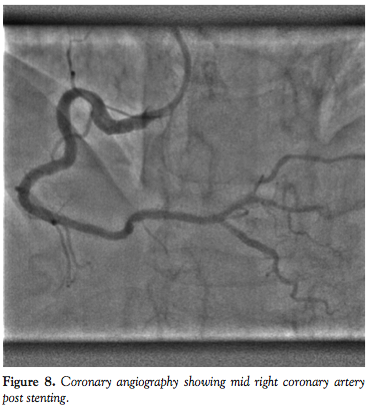

Acute procedural success was achieved in 33 patients (94%) using conventional PCI techniques. Predilatation was performed in 31 patients (89%) and buddy wires were used in 12 patients (34.3%). For the 2 cases (6%) in which stent delivery failed, Heartrail catheters (the so-called “five-in-six” system; Terumo) were used as a bail-out to facilitate stent delivery. For the first Heartrail patient, the lesion was located in the distal RCA and the major impediment to stent delivery (besides the underlying tortuosity) was the presence of 3 long overlapping stents that were previously implanted in the proximal to mid RCA. The second Heartrail patient had lesions in the mid and distal RCA, but the stent passage was largely impeded by extreme tortuosity in the proximal RCA, which had moderate calcification.

For the overall study group, there were no peri- or postprocedural MACEs. Mean fluoroscopic time was 25.3 ± 17.2 minutes and mean contrast volume was 203.1 ± 80.1 mL. Figures 1 through 8 illustrate our experiences with Integrity coronary stents in some of the “classical” tortuous coronary vessels.

One striking feature we observed about the Integrity coronary stent was that it conformed very well to the vessel wall (Figures 1-8). This is important, since it means the stent has sufficient radial strength to resist the elastic recoil of the media and can mold its shape along the contour of a curved segment with minimal vessel straightening and provide a large desired lumen. When the DES is implanted, excellent apposition of the struts on the vessel wall will ensure uniform delivery of the cytostatic drug to prevent neointimal hyperplasia. An in vitro conformability test15 has shown the Integrity DES to have better strut apposition and lower vessel wall stress when compared to other market-leading DESs. This has